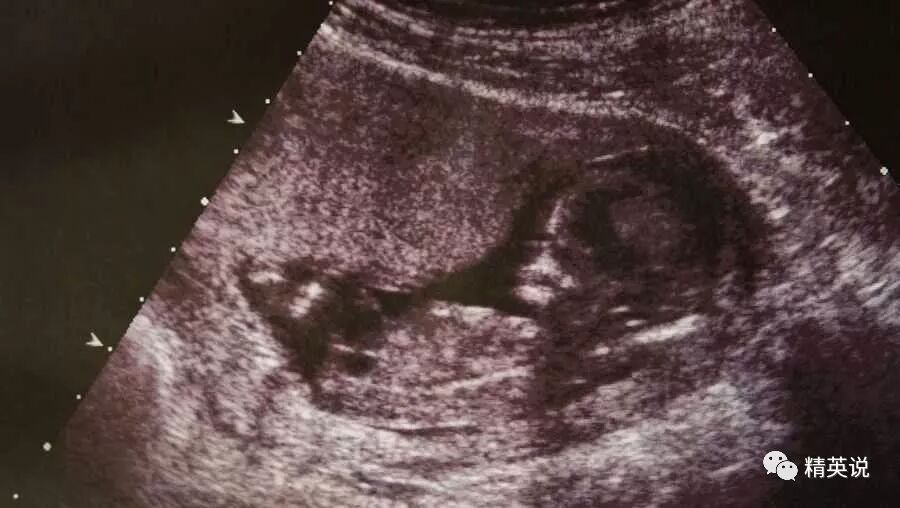

生过宝宝的妈妈都知道,胎儿一般在六周左右就能够侦测到心跳,但这个时候,它仅仅只有一颗豌豆的大小。

那么,根据乔治亚州的法律规定,这个时候它就已经被承认为自然人。这也意味着,如果女性在6周以后,再决定把这颗“豌豆大小”的胚胎堕掉,就将按照杀人罪处理。因为,这些行为,都导致了“一个自然人的死亡”。

而怀孕六周,对于女性来说,又是什么概念呢?

这个时候,女性往往都不知道她们自己已经怀孕了。月经推迟两周,对于很多女性来说都是很正常的事情,月经不调,或是因为压力而导致推迟,都极其常见。

而一颗豌豆大小的胚胎,更是毫无存在感,不会有孕吐,更不会有妊娠反应。而她们一旦错过了合法堕胎的时机,就不得不将其生下来。